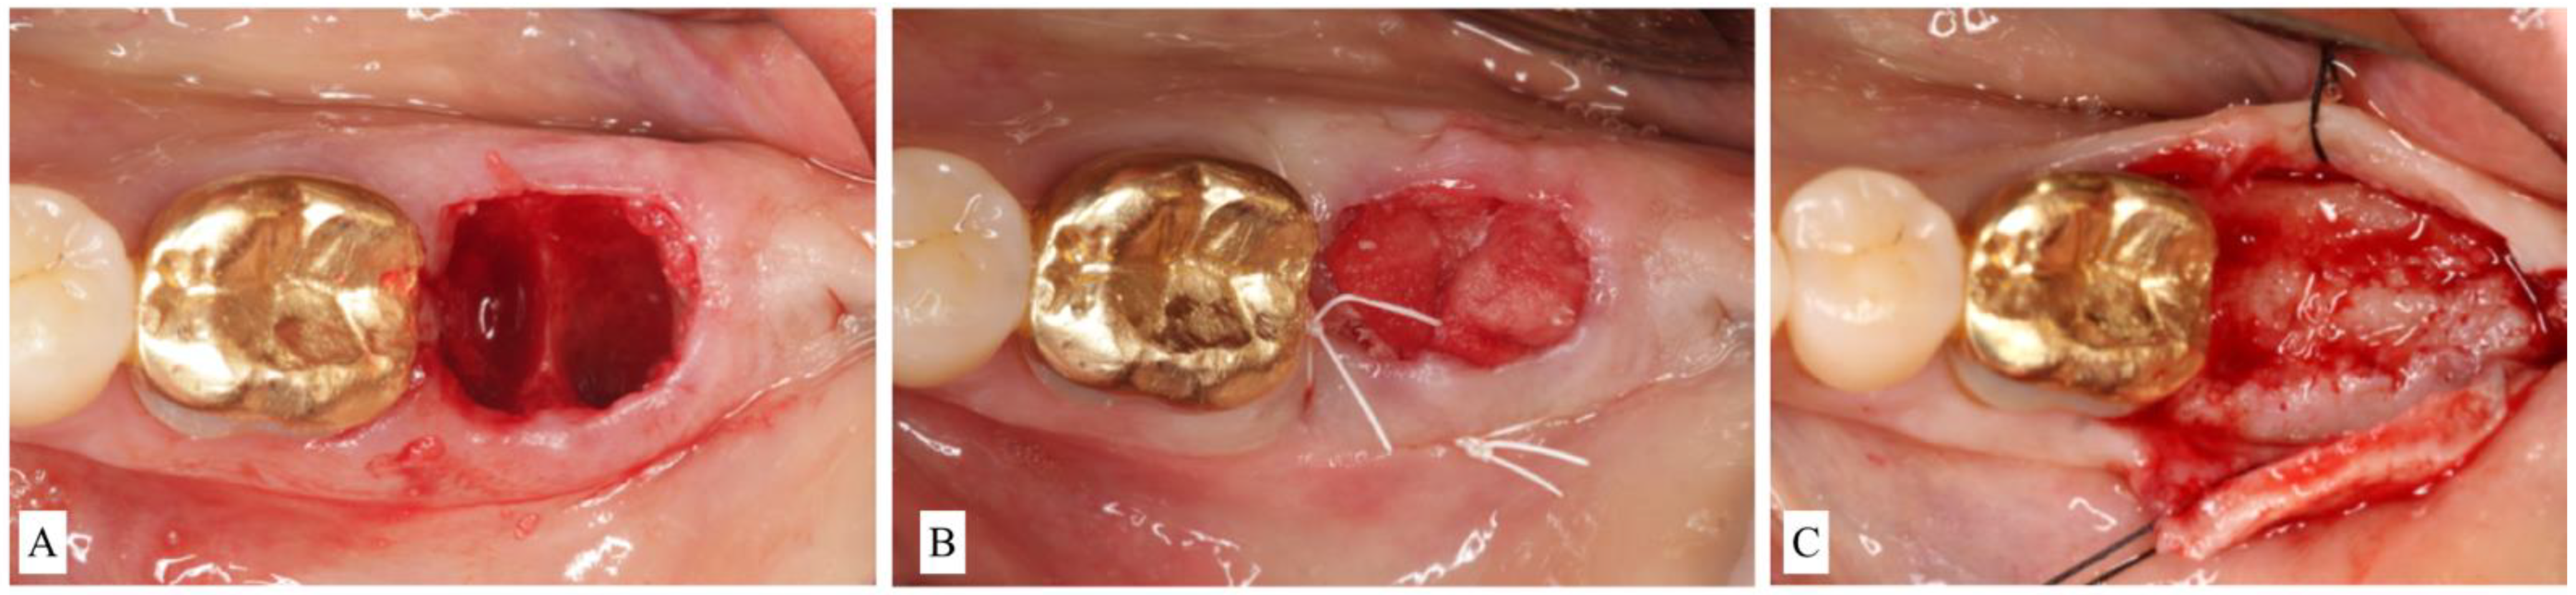

- ST1B sockets are treated with a particulate allograft or xenograft placed inside the alveolus. Bone-grafting material is applied to fill the extraction socket 1–2 mm below the alveolar crest. The remaining coronal aspect is then sealed either by a bioabsorbable collagen plug wound dressing matrix [22,23] or by an autogenous soft-tissue graft especially in a highly esthetically demanding maxillary anterior region [24] (Figure 3A–C).